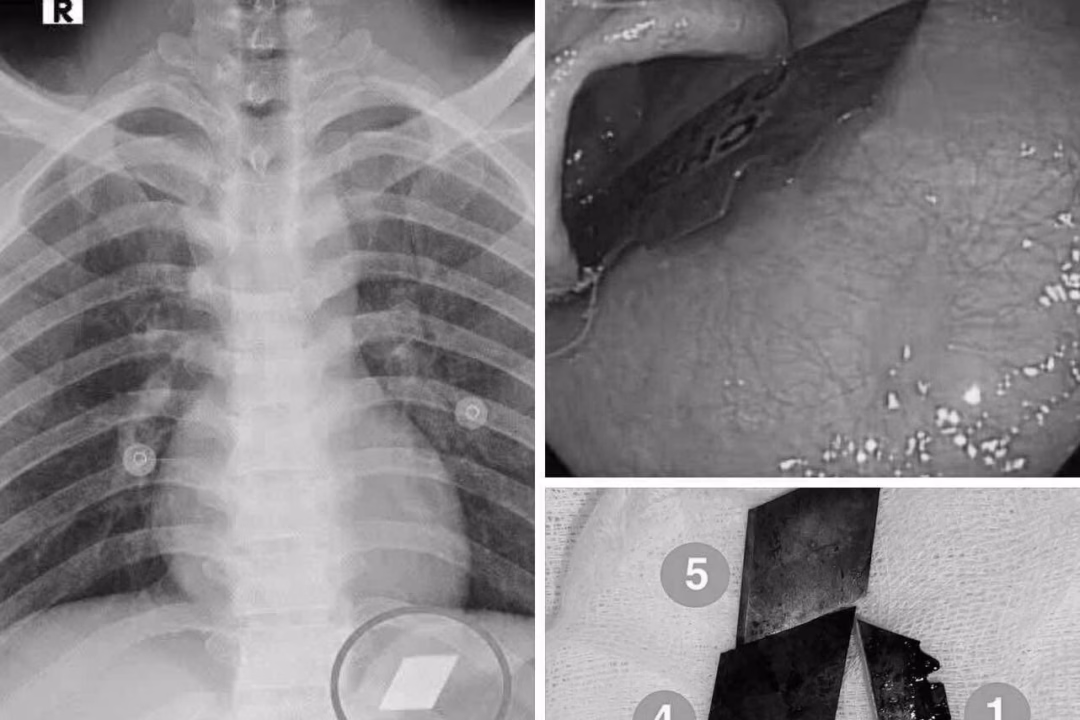

Qua quá trình thăm khám và chụp X-quang, các bác sĩ đã phát hiện ra các dị vật cản quang nằm tại vị trí dạ dày. Ngay lập tức, bệnh nhân được chỉ định tiến hành nội soi cấp cứu để gắp bỏ những dị vật này. Sự thành công của ca thủ thuật này là nhờ vào sự phối hợp chặt chẽ và hiệu quả giữa ê-kíp nội soi và gây mê.

Các bác sĩ đã thành công trong việc gắp ra 4 lưỡi dao rọc giấy ra khỏi dạ dày và một phần lưỡi dao lam bị mắc tại vùng hạ họng – miệng thực quản. Sau khi hoàn thành thủ thuật, bệnh nhân được theo dõi sát tình trạng và đã ổn định sức khỏe, xuất viện trong tình trạng an toàn.